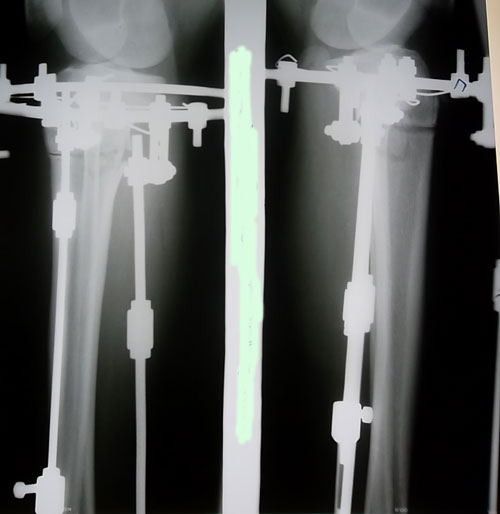

- Диагноз: О- образная деформация нижних конечностей